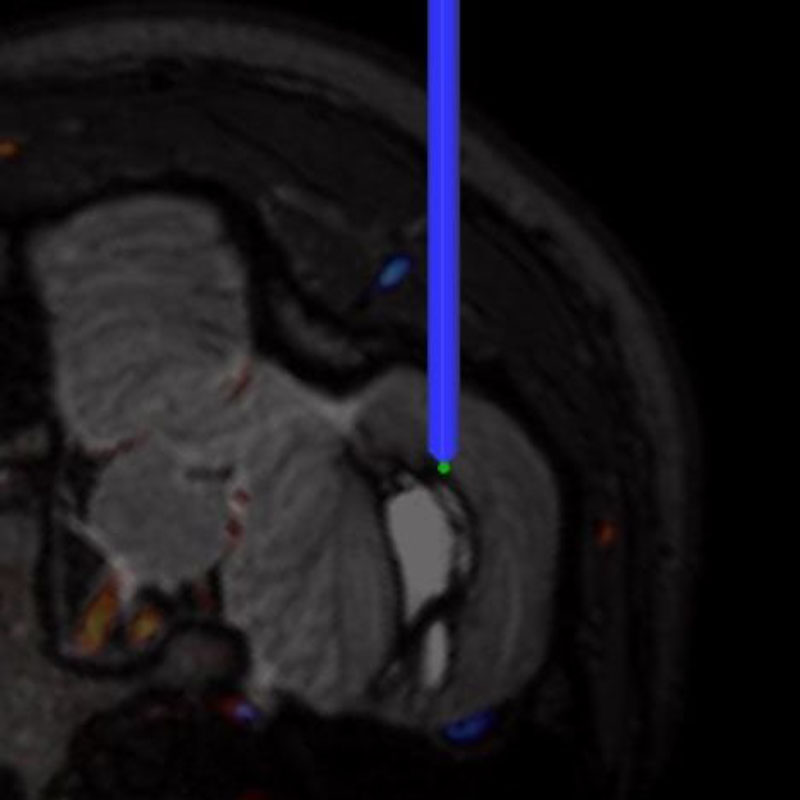

No.359 モニタリング

No.359 手術前

No.359 手術中

No.359 手術後

出血既往があり。2回の手術前血管内手術の後に、

Lateral transpeduncular approachにより再々出血予防を目的に

摘出手術を行う。完全摘出であることを確認した。

手術による合併症や後遺症なしで退院した。経過良好。